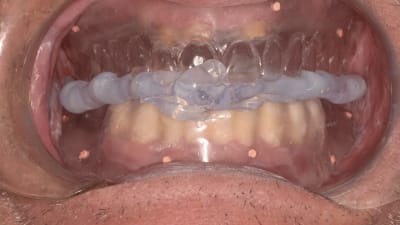

Case Reports Implantology Prosthodontics CAD/CAM Fabrication of Definitive Implant Prostheses: A Digital Workflow From Planning to Implant Placement to Final Restoration By Harold S. Baumgarten, DMD December 01, 2015 10 min read

Clinical Technique Review Implantology Salvaging Implants With an Nd:YAG Laser: A Novel Approach to a Growing Problem By Jon B. Suzuki, DDS December 01, 2015 13 min read